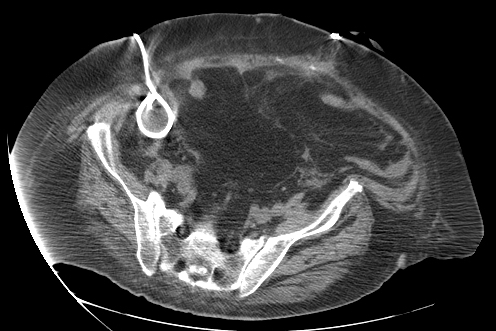

Abscess Drainage: Case 1

23 year old female with fever and RLQ tenderness s/p appendectomy.

Comment: This case demonstrates performance of a straight-forward CT-guided drainage. Once the abscess was localized on CT and the access site confirmed with a 25g needle, the collection was accessed with a Chiba needle and a guidewire was coiled within the collection. Serial dilatation was then performed so that a pigtail drainage catheter could be placed within the collection for drainage.